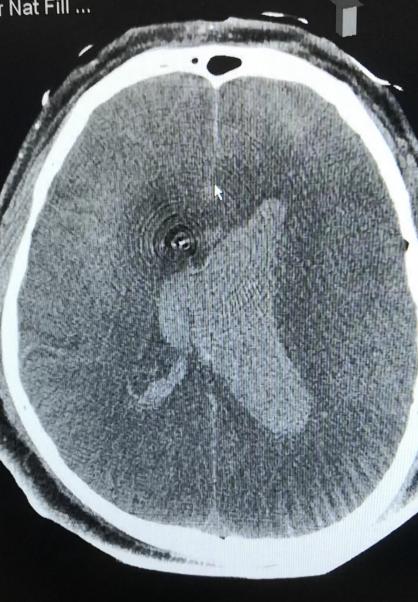

患者韩先生,入院3天前洗澡后出现头痛头晕,未诊治,因症状加重前来清华大学附属垂杨柳医院神经内科门诊就诊。期间,患者头痛剧烈,伴恶心呕吐,被紧急送至急诊科,头颅CT提示蛛网膜下腔出血、脑室出血(Fisher分级4级)。随即患者出现昏迷,GCS5分,呼吸困难,急诊行气管插管,呼吸机辅助呼吸,并联系医院神经外科前来急会诊。

▲头颅CT显示广泛蛛网膜下腔出血,脑室积血